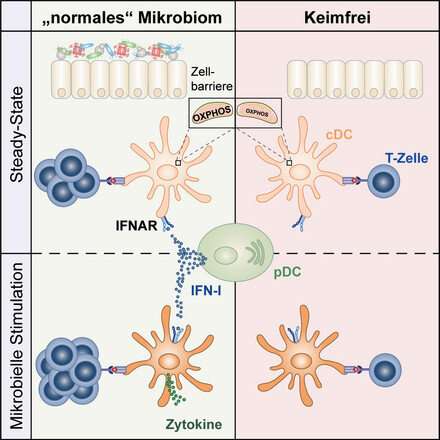

Immagine: gli interferoni di tipo I indotti dal microbiota controllano la funzionalità delle cellule dendritiche. Credito: Schaupp / Charité.

Il team di ricercatori guidato dal Prof. Diefenbach ha scoperto che le cellule dendritiche non sono in grado di innescare risposte immunitarie in condizioni sterili (cioè nei topi privi di germi). I ricercatori hanno concluso che le cellule dendritiche devono ricevere informazioni mentre la cellula si trova nel suo stato basale, che è caratterizzato dall’assenza di infezione, e che queste informazioni devono derivare dal microbioma. Questi segnali derivati dal microbioma innescano ile cellule dendritiche per una futura risposta contro i patogeni.

“Vogliamo comprendere la natura degli effetti continui del microbioma sulla funzione delle cellule dendritiche”, afferma il Prof. Diefenbach. “In questo studio, siamo stati in grado di dimostrare che nel loro stato basale, queste cellule immunitarie specializzate sono soggette alla segnalazione ininterrotta controllata da microbiomi, di interferoni di tipo I (IFN-I)”.

Gli interferoni sono citochine, molecole di segnalazione speciali note per svolgere un ruolo nell’attività antivirale. “Fino ad ora, avevamo saputo solo poco del ruolo dell’IFN-I nello stato basale. Le cellule dendritiche che non ricevono questa segnalazione IFN-I durante lo stato basale non possono adempiere alle funzioni fisiologiche che svolgono nell’ambito della lotta del corpo contro i patogeni “, afferma il microbiologo. I risultati dello studio suggeriscono che il microbioma controlla l’idoneità del sistema immunitario. Esercita questo controllo portando il sistema immunitario in uno stato di “prontezza” al fine di accelerare la sua risposta ai patogeni.

Descrivendo le osservazioni dei ricercatori, la prima autrice dello studio, Laura Schaupp, afferma: “È interessante notare che, quando abbiamo esaminato le cellule dendritiche da animali privi di germi e quelli senza segnalazione IFN-I, siamo stati in grado di osservare bassi livelli di espressione tra i geni coinvolti nella catena respiratoria mitocondriale. Ulteriori analisi hanno rivelato che il metabolismo cellulare delle cellule dendritiche da animali senza germi è disfunzionale, il che li rende incapaci di avviare una risposta immunitaria. Ciò suggerisce che il microbioma è di cruciale importanza per il funzionamento delle cellule dendritiche.